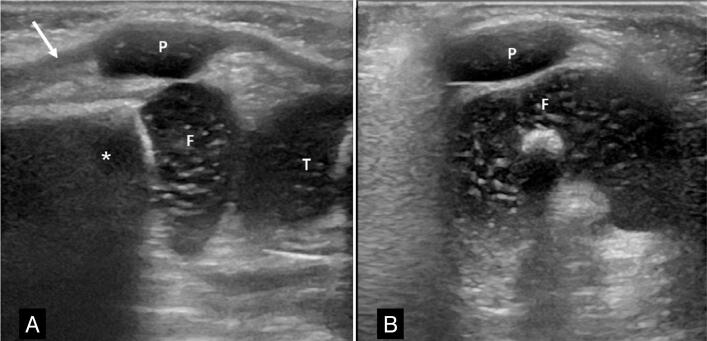

Objective: To analyze cases with clinical suspicion of patellar abnormalities, before ossification of the patella and to characterize the spectrum of abnormalities of the cartilaginous infantile patella by ultrasonography.

Results: Twelve patients with suspected patellar abnormalities were identified, with a mean age of 9 months and 4 days (±1.9 years), 75% male.

Findings: dislocation or subluxation associated with patellar hypoplasia (7 knees), low lying patella and patellar hypoplasia (2), unilateral patellar agenesis (1), bilateral patellar agenesis (1), patellar instability in dynamic assessment and absence of patellar morphological changes (1). In two patients, ultrasonography was negative. The craniocaudal diameter of the hypoplastic patellas measured 0.94 cm ± 0.24 cm and in the control group 1.24 cm and ±0.12 cm (p<0.01). The Insall-Salvati index adapted for ultrasonography measured 0.63±0.07 for the low lying patella and 0.93±0.16 in the control group (p=0.004).

Conclusions: Ultrasonography was useful to characterize abnormalities of the cartilaginous patella, and the most frequent findings were instability and hypoplasia. Level of Evidence IV; Case Series.